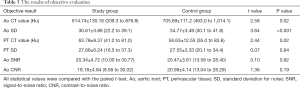

The objective measurement results are listed in Table 3. Both groups had adequate contrast enhancement in vessels. The control group had a 14.8% higher CT value (705.89±111.20 vs. 614.74±127.73 HU) and a 13.6% higher SD value (34.77±3.49 vs. 30.61±3.88 HU) in the aorta than the study group (P<0.05). The study group had a 12.6% higher CT value in PT (63.78±9.37 vs. 56.63±12.55 HU, P<0.05), but a similar SD value (27.66±6.24 vs. 27.55±3.33, P=0.94) compared with the control group. SNR (20.34±4.72 vs. 20.47±3.61) and CNR (19.18±4.84 vs. 20.99±4.14) for the aorta had no statistically significant differences between the 2 groups (P>0.05). Interobserver agreement was substantial concerning the overall image quality (k =0.79, P<0.05).